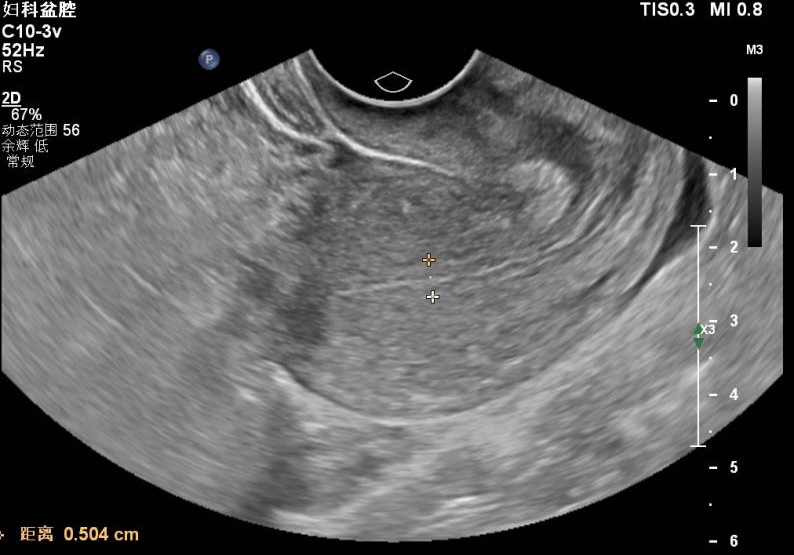

患者张xx,女,29岁。就诊时间:2021年3月20日。 主诉:继发性痛经伴进行性加重2+年。 现病史:患者自2018年10月份开始无明显诱因出现月经期下腹痛,起初未在意,未就诊。现因痛经进行性加重,NRS疼痛评分5分,伴性交痛,为进一步诊治就诊。 既往史:既往体健,无特殊既往史可询。 个人史:无特殊个人史可询。 月经史:14岁初潮,5/28天,经量中等,2018年开始出现痛经。 婚育史:22岁结婚,孕2产1,2015年足月顺产分娩1女,2017年自然流产1次。 家族史:无特殊家族史可询。 妇科检查:外阴已产式,阴道畅,宫颈光滑,大小正常,质中,子宫后位,宫体大小正常,形态规则,活动欠佳,后穹隆可及触痛结节,右侧附件区可扪及一个大小约7cm*6cm*5cm的囊性肿物,活动欠佳,伴触痛,左侧附件区未扪及明显异常。 辅助检查: B超:子宫后位,宫体大小正常,宫腔线居中,内膜厚4mm,肌层无明显增厚,右侧附件区可见大小约76mm*58mm*54mm的囊性肿物,内可见密集细弱光点,左侧附件区未见显异常回声。 术前B超:右侧卵巢囊肿 诊断: 诊断依据: 处理:患者继发性痛经伴进行性加重,B超检查提示卵巢子宫内膜异位囊肿>4cm,患者近期内有生育要求,予以行腹腔镜下卵巢子宫内膜异位囊肿剥除术+盆腔子宫内膜异位病灶切除术,术后予以地屈孕酮口服减少内异症复发并随访。 1.诊疗思路: (1)长期管理,坚持以临床问题为导向,以患者为中心,分年龄阶段处理,综合治疗; (2)基于临床诊断尽早开始经验性药物治疗; (3)规范手术时机,注意保护卵巢功能和生育力,使患者的手术获益最大化; (4)保守性手术后进行药物长期管理,综合治疗,预防复发; (5)内异症患者应定期复查,对有恶变高危因素的患者应警惕恶变。 患者继发性痛经伴进行性加重,B超检查提示卵巢子宫内膜异位囊肿>4cm,根据中国子宫内膜异位症诊治指南(第三版),有手术指征,针对该患者的病情,我们采取了腹腔镜手术+术后药物长期管理的治疗策略,并鼓励患者恢复后尽早备孕。 2.手术治疗: 术后病理: (1)右侧卵巢子宫内膜异位囊肿; (2)(盆腔病灶)可见含铁血黄素陈旧,考虑为子宫内膜异位; (3)患者术后恢复良好,于2021年3月26日出院。 3.术后长期管理: 4.术后随访: 妇科检查:阴道后穹隆触痛结节不明显,双侧附件区未扪及明显异常。复查盆腔彩超未提示巧囊复发。嘱患者继续规律服药。 第一次复查 ②2021-12-06,患者第二次随访。痛经情况较术前明显缓解,NRS疼痛评分1分。患者期间一直遵医嘱规律服用地屈孕酮,月经正常。 妇科检查:阴道后穹隆未扪及触痛结节,双侧附件区未扪及明显异常。复查盆腔彩超未提示巧囊复发。嘱患者继续规律服药。 第二次复查 ③2022-04-17,患者第三次随访。患者自术后已规律服用地屈孕酮1年,月经正常,痛经已完全缓解,无性交痛,NRS疼痛评分0分。 妇科检查:阴道后穹隆未扪及触痛结节,双侧附件区未扪及明显异常。复查盆腔彩超未提示巧囊复发。建议患者可继续规律服用地屈孕酮。 第三次复查 子宫内膜异位症是生育期女性的常见病,多发病,约10%的生育期女性患有内异症。其主要症状是下腹痛和痛经,还可表现为慢性盆腔痛和性交痛,除此之外还有不孕、月经异常等表现。内异症可影响生殖系统各个部分,导致卵巢功能受损,生育力下降。2021年中国子宫内膜异位症诊治指南(第三版)指出内异症治疗应以患者为中心,分年龄阶段处理,规范手术时机,在保守性手术后应予以长期药物管理及定期复查[1]。 内异症的药物治疗主要分为非甾体类抗炎药(NSAID)、孕激素类、复方口服避孕药(COC)、促性腺激素释放激素激动剂(GnRH-a)及中药等。其中孕激素又包括地屈孕酮和高效孕激素,如地诺孕素、甲羟孕酮、左炔诺孕酮宫内释放系统(LNG-IUS)[2-3]。 地屈孕酮的优势在于控制内异症的同时不抑制排卵,适合有生育需求的患者[4]。全周期口服地屈孕酮片10-20mg/d,可有效控制内异症,同时可改善孕激素抵抗,增加妊娠机会[5]。 本病例中患者有明确的近期内生育要求,故不适宜予以GnRH-a、COC、地诺孕素等药物;同时患者EFI评分7分,患者拒绝试管婴儿等辅助生殖技术。因此,我们在与患者及家属沟通后给予患者月经第5-25天,地屈孕酮10mg/d,口服来减少内异症的复发并在服药前给患者做了乳腺彩超排除了乳腺结节。患者服药3个月即感到痛经明显缓解,术后规律服药1年后痛经完全消失,起到了良好的治疗效果。地屈孕酮得益于其服药期间不干扰受精卵着床,增强自然受孕能力,对有生育需求的患者具有优势[6]。同时,长期服用地屈孕酮对肝脏影响小,不引起骨质疏松,是内异症长期管理的优选药物之一[7-8]。 参考文献: 赵晨阳 医生 湖南省郴州市第一人民医院(湘南学院第一附属医院) 湖南省郴州市第一人民医院(湘南学院第一附属医院)妇科 副主任医师,医学硕士,毕业于中南大学湘雅医学院 ❖湖南省郴州市妇产科专业委员会秘书 ❖主攻方向:妇科恶性肿瘤规范化治疗和妇科微创手术 ❖目前主持湘南学院校级课题1项,院级课题1项,院内新技术项目1项

3.B超检查提示右侧附件区可见大小约76mm*58mm*54mm的囊性肿物,内可见密集细弱光点。